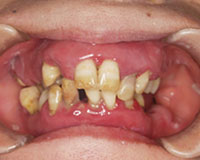

口の中全体の歯茎が腫れ上がっており、ほとんど物がかめないということで来院されました。

全体的に歯肉がはれている、歯ブラシをすると血と膿が出ていて口臭もする

治療前

全体に歯茎が腫れ上がってしまい歯が動いて、噛み合わせが大きく崩れている。.

重度の歯周病により、歯を支える骨がほとんど溶けてしまっており、歯がグラグラとなり咬み合わせが大きく崩れている。